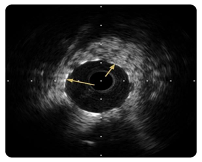

What are the arrows pointing to in the images below?

dissection